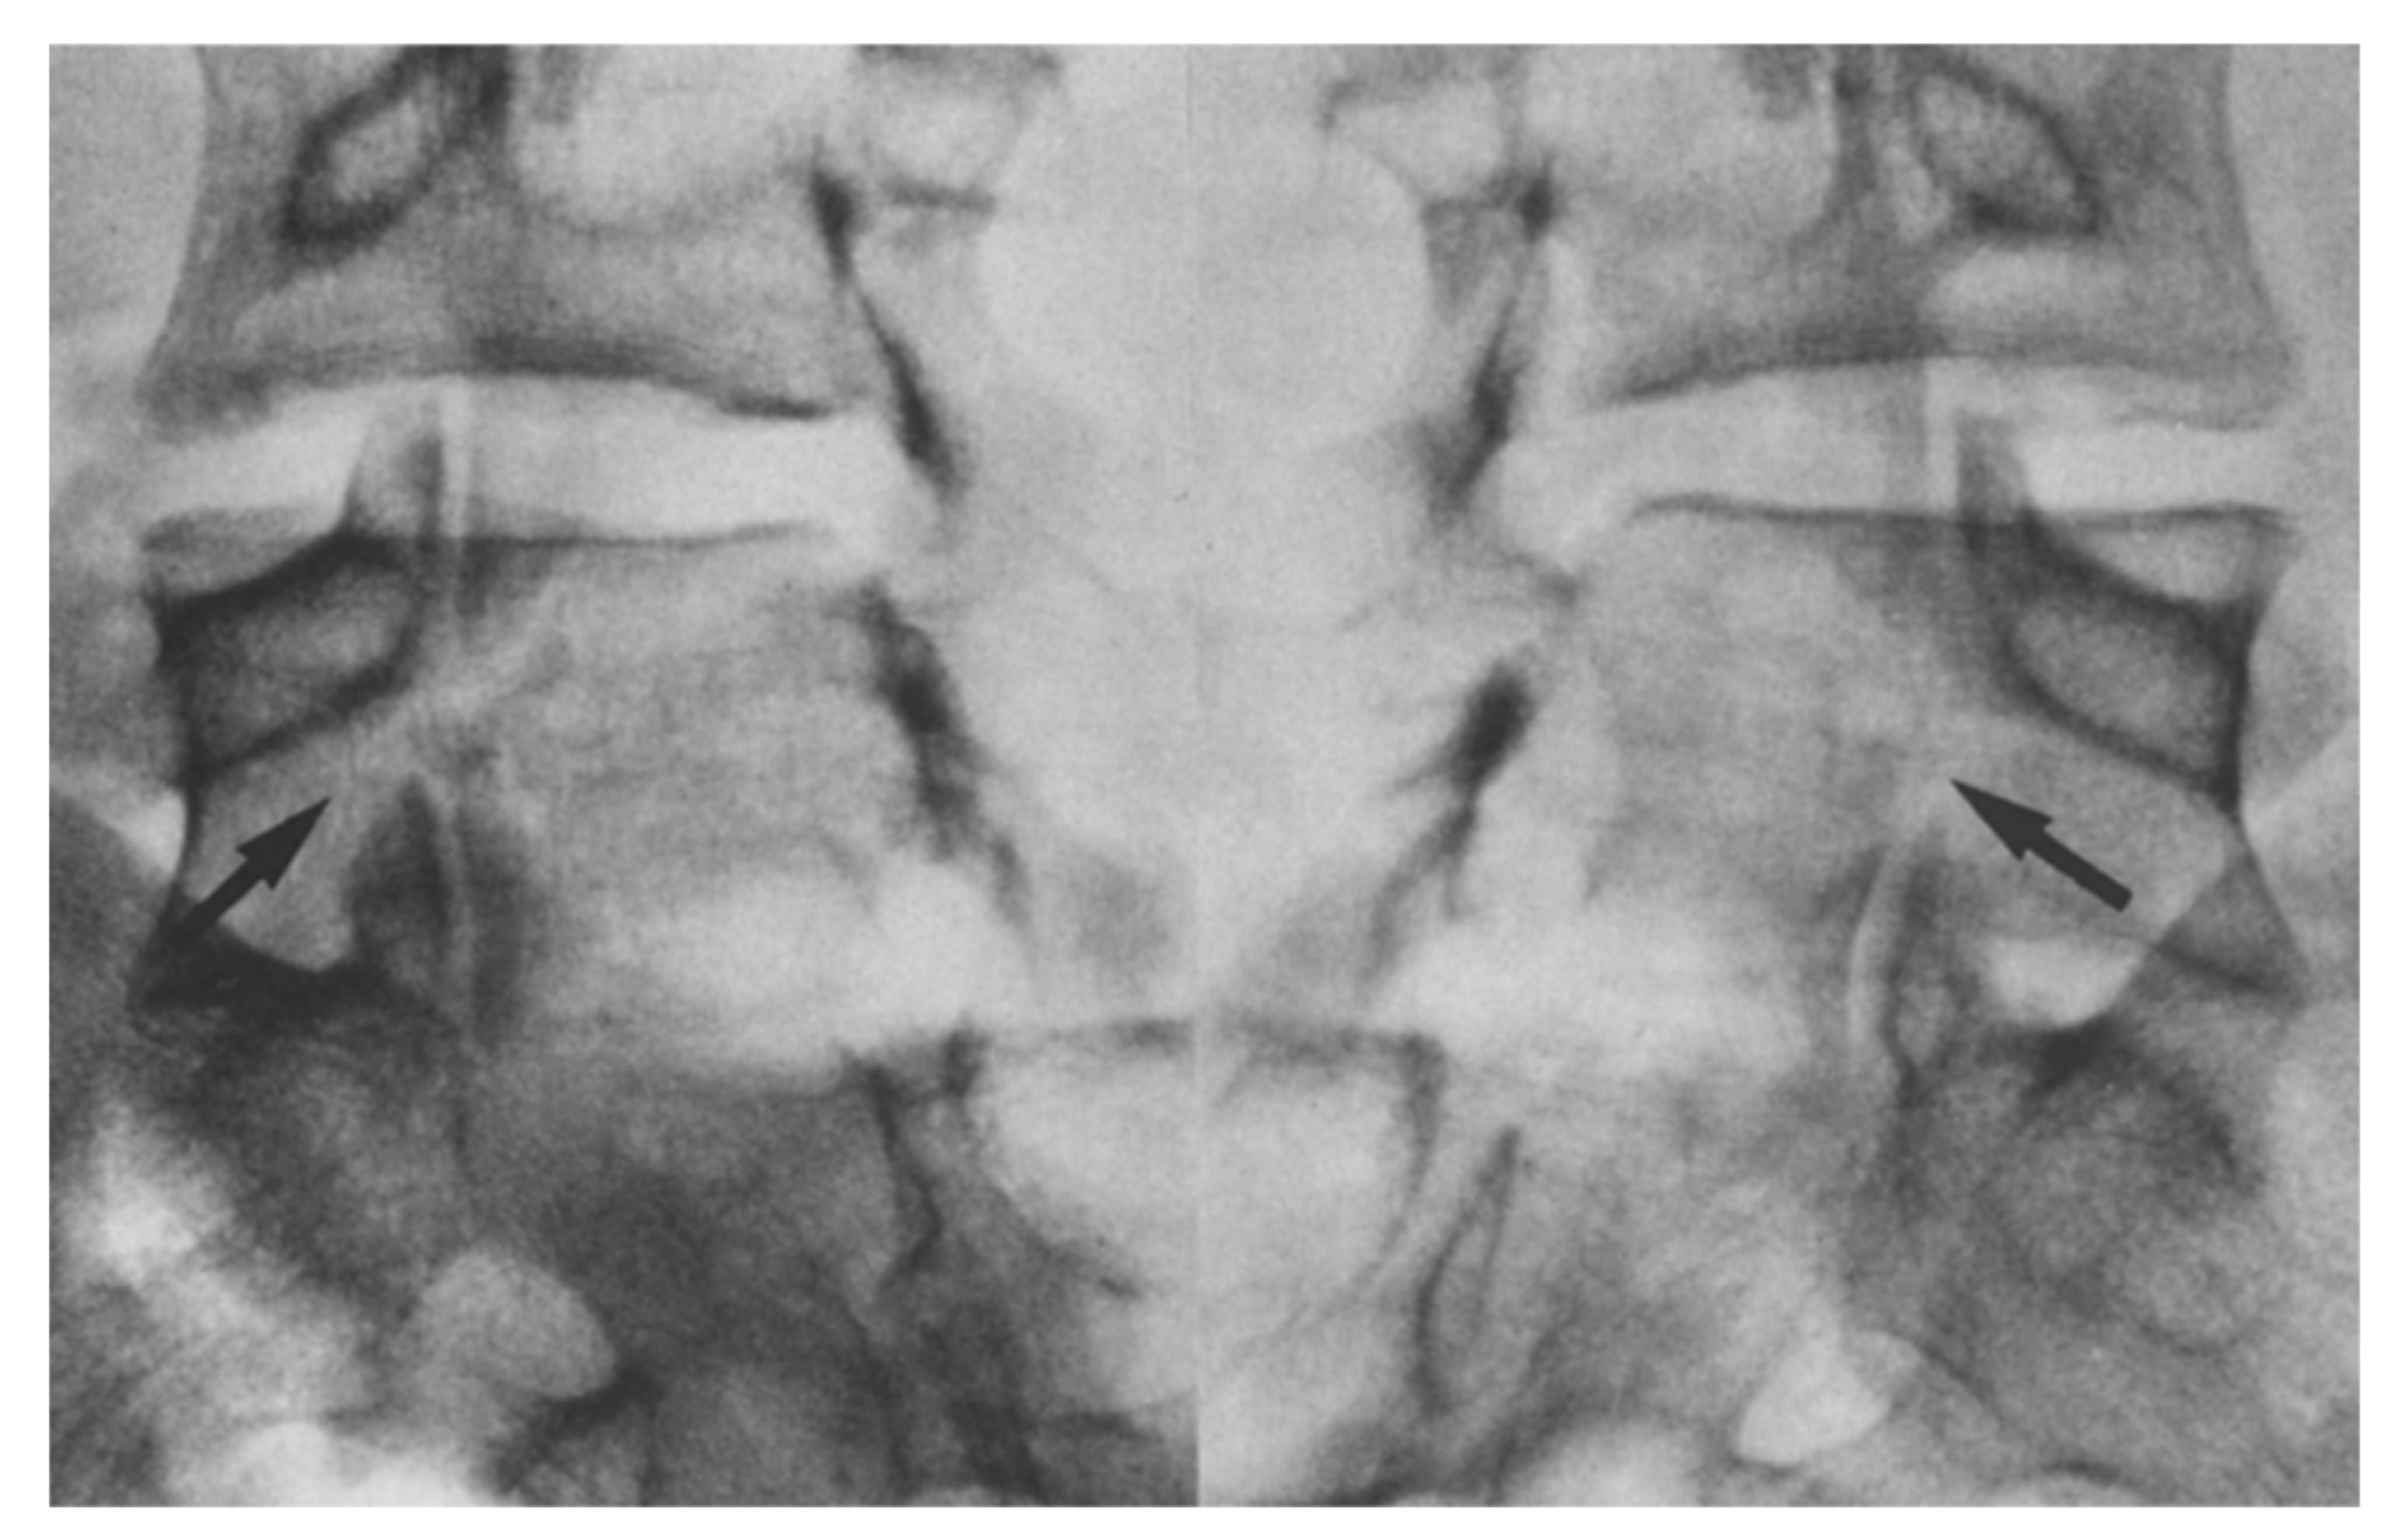

- Nicol, R.O.; Scott, J.H. Lytic spondylolysis. Repair by wiring. Spine 1986, 11, 1027–1030. [Google Scholar] [CrossRef]

- Johnson, G.V.; Thompson, A.G. The Scott wiring technique for direct repair of lumbar spondylolysis. J. Bone Jt. Surg. Br. Vol. 1992, 74, 426–430. [Google Scholar] [CrossRef]

- Hioki, A.; Miyamoto, K.; Sadamasu, A.; Nozawa, S.; Ogawa, H.; Fushimi, K.; Hosoe, H.; Shimizu, K. Repair of pars defects by segmental transverse wiring for athletes with symptomatic spondylolysis: Relationship between bony union and postoperative symptoms. Spine 2012, 37, 802–807. [Google Scholar] [CrossRef] [PubMed]